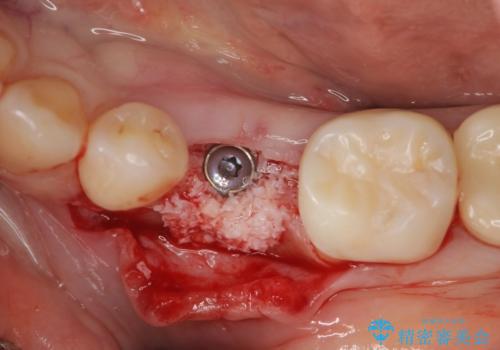

乳歯を抜去して歯ぐきの状態が落ち着いたのち、骨の増成を伴うインプラント治療を行い機能の回復を図ります。

残念ながらぐらつきが大きくなり、残すことが難しくなり抜去したのちインプラントを用いて咬合機能の回復をしっかりと行いました。